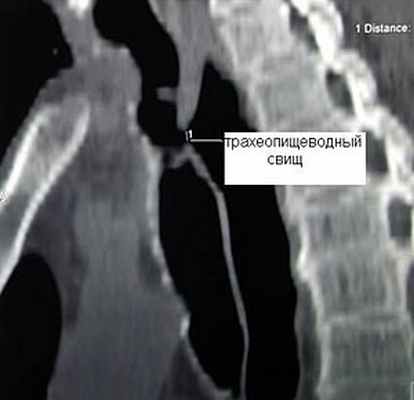

Трахеопищеводные свищи

Наиболее часто трахеопищеводные свищи возникают у больных раком пищевода при распаде опухоли, прорастающей в трахею. Другими причинами являются ранения пищевода и трахеи, перфорация пищевода при его бужировании по поводу рубцовых стриктур, пролежень от трахеостомической и интубационной трубок при длительной искусственной вентиляции легких.

Частота трахеопищеводных свищей не превышает 0,5% среди больных, которым проводилась длительная искусственная вентиляция легких. Как правило, трахеопищеводные свищи у этой группы больных возникают от избыточного давления манжетки интубационной трубки или давления дистального конца трахеостомической трубки на заднюю стенку трахеи при наличии в пищеводе зонда для энтерального питания, что приводит к ее ишемии, некрозу и образованию соустья между пищеводом и трахеей. Часто трахеопищеводные свищи сочетаются со стенозом трахеи, что существенно осложняет лечение таких больных. Заброс пищи в трахею приводит к гнойному трахеобронхиту с последующим развитием абсцедирующей пневмонии, что значительно ухудшает прогноз заболевания. Питание у такого рода больных через рот исключается. Адекватное питание больного обеспечивается через энтеральный зонд или гастростому. Учитывая, что консервативное лечение больных с трахеопищеводными свищами малоэффективно, единственным радикальным способом ликвидации свища неопухолевой природы является оперативное вмешательство.

Клиническая диагностика трахеопищеводных свищей, как правило, не вызывает трудностей. Проявляются они приступообразным кашлем, который возникает во время приема пищи. Однако уточнение их локализации при рентгенологическом исследовании с барием и эзофагоскопии вызывает существенные трудности, особенно при небольших размерах свища. Более информативным оказывается трахеоскопия, при которой удается определить размеры свища, расстояние от голосовых связок и карины. Кроме того, значительную помощь в выявлении трахеопищеводных свищей оказывает также компьютерная томография.

![]() Рис.9. Компьютерная томограмма больного с трахеопищеводным свищом. | ![]() Рис. 10. Трахеоскопия больного с трахеопищеводным свищом, осложненным стенозом трахеи. |